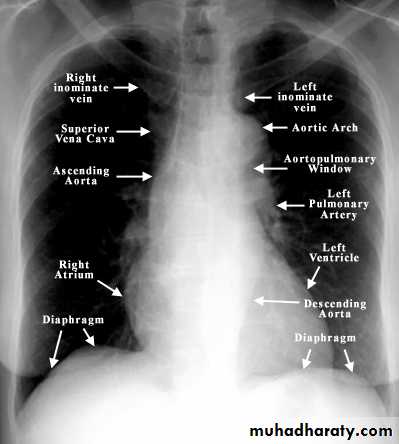

3- check position of heart and mediastinum: normally trachea lies midway or slightly to right of midpoint between medial end of clavicles.

One third of heart is on rt. Of midline and two thirds to left.

4- looks at mediastinum: the outline of heart and med. Should be clearly seen except where the heart lies in contact with the diaphragm.

The rt. Sup. Med. Border is usually straightly or slightly curved.

Left sup. Med. Border is ill defined above aortic arch.

With increasing age the aorta elongates, lead to unfolding of aorta because aorta fixed at aortic valve and diaphragm, lead to ascending aorta deviate to rt., descending aorta deviate to left.